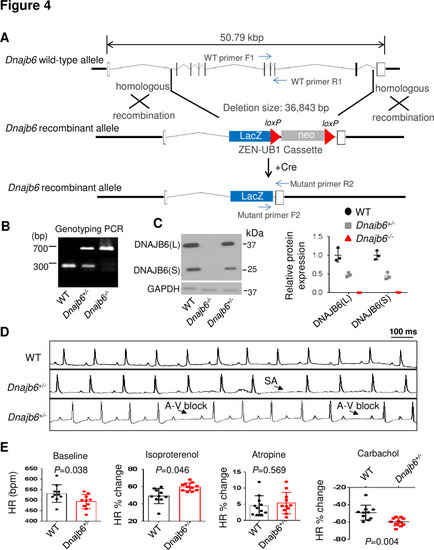

Dnajb6+/- mice exhibited increased incidence of SA and AVB and impaired response to autonomic stimuli. (A) Schematics of the Dnajb6 knockout (KO) mice. The insertion of Velocigene cassette ZEN-Ub1 created a deletion of 36,843 bp nucleotides spanning from the first to the last intron of the Dnajb6 gene at the Chromosome 5. The neomycin selection cassette was excised after crossed to a Cre expression line. (B) Representative DNA gel images of PCR genotyping for identifying WT (300 bp), Dnajb6+/- heterozygous (hets), and Dnajb6-/-homozygous (homo) mutant alleles . (C) Western blotting and quantification of DNAJB6 short (S) and long (L) protein expression in WT and Dnajb6 mutants. N=3 animal per group. (D) Shown are representative ECG recordings results showing SA and AVB phenotypes detected in the Dnajb6+/- mice at 6 months. (E) The Dnajb6+/- mice manifests impaired response to different autonomic stimuli. N=10–12 mice per group, unpaired student’s t-test. SA, sinus arrest. AVB, atrioventricular block. |